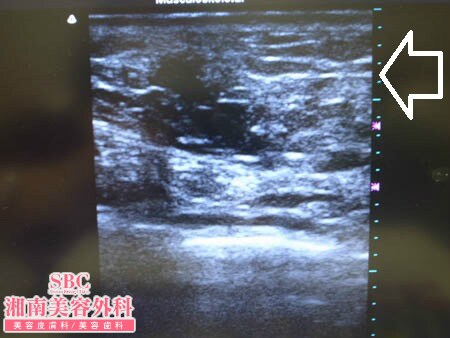

No.136523【脂肪吸引】YouTube手術関連動画掲載数・世界第一位! あの有名な根こそぎ竹田先生の劇的ビフォーアフター!〜3回目の二の腕の脂肪吸引の結果に大満足しておなかの脂肪吸引を託す!術中3Dタッチビュー・上腹部〜